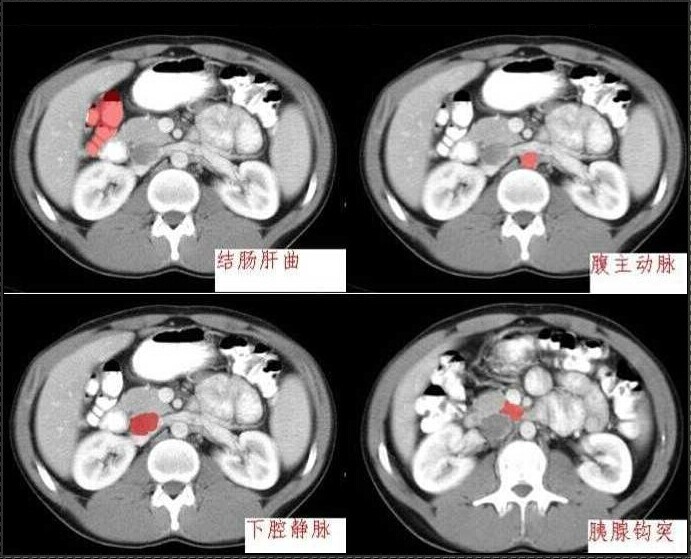

十分钟学会腹部CT解剖(多图)